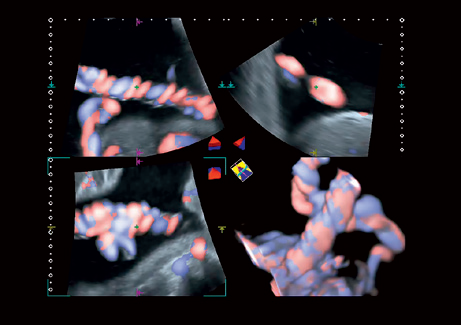

• STIC - исследование сердца плода в режиме объёмной визуализации

• 3D Color - цветное 3-х мерное изображение

• STIC Color - цветная объёмная визуализация сердца плода

• Программа анализа сердца плода в трех проекциях в реальном времени 4D Stick;